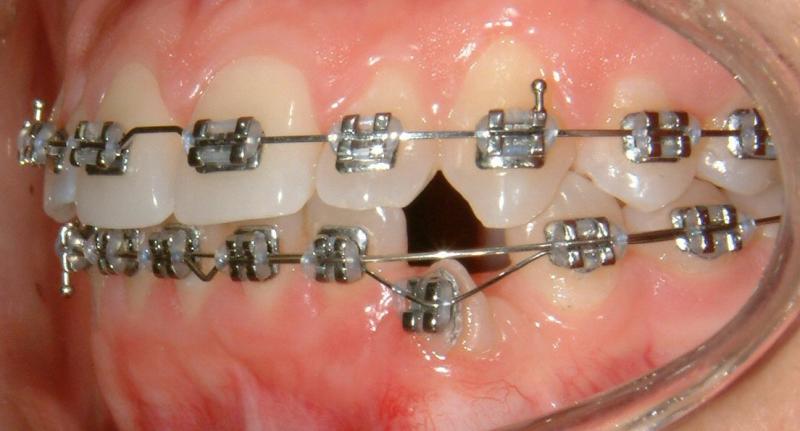

The progress of tooth eruption is complete (Fig. 24). Note that the crown of the tooth (lower left canine) is surrounded by healthy gingiva.

Fig. 24 Complete eruption, healthy gingiva, 9 months after surgical exposure (progress)

© Copyright 2007-2014, Vu Orthodontics. All rights reserved.